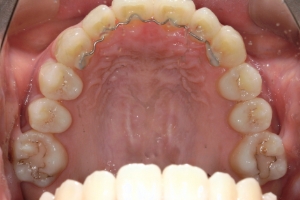

AFTER

治療後

下の前歯が上あごの歯ぐきに当たるほど噛み合わせが深く、そのことが原因で上顎歯列の正中にすき間(正中離開)が生じていました。部分矯正ですき間を無理やり閉じても、噛み合わせが深いままでは治療後の再発リスクが高くなります。そのため全体矯正で奥歯の噛み合わせを整え、噛み合わせを浅くしつつ前歯を並べました。正中離開は戻りやすい傾向があるので、再発を防ぐため固定式リテーナーを推奨しています。